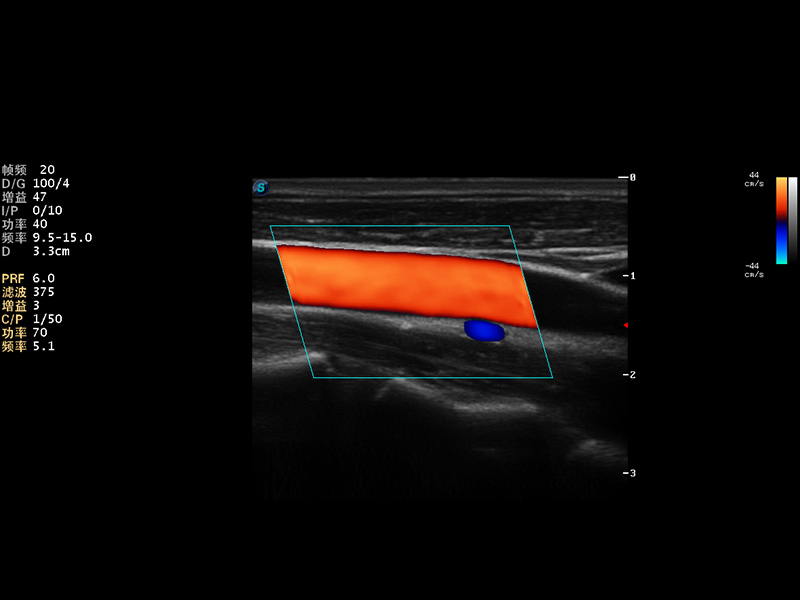

S9便携式彩色多普勒超声诊断仪是亚星官网研发的高端便携彩超设备,外观设计新颖、产品性能卓越。S9在便携超声领域采用了突破传统的触摸屏交互设计,并以先进的软件硬件技术和设计理念,为您带来清晰的图像质量、稳定的工作性能和便捷的操作体验。

AutoC智能血流追踪